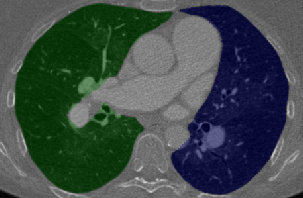

For determining a measure for pulmonary blood pressure, a segmentation of the blood vessels inside the lung is needed. We present a robust algorithm that combines lung- and airway-segmentation, together with a sophisticated vessel enhancement filter to obtain a proper segmentation of the left and right pulmonary vessel trees, even in patients showing severe pathologies. A schematic of the anatomy of the human lung is shown in Figure 1.

At the core of our method is a multi-scale vessel enhancement (VE) filter based on the Hessian matrix. It is similar to [15] in using the eigenvectors of the Hessian matrix to detect candidate voxels inside the vessels, and computing an offset-medialness boundary measure perpendicular to the estimated vessel direction [10]. The VE response (i.e. medialness) is limited to the right and left lung, which is derived from an intensity-based lung segmentation and a coarse airway tree segmentation with a labelling of left and right main bronchi. After centerline detection from the VE response, a coarse radius estimation of the vessel is obtained using a spherical ray-casting approach. The final segmentation is the output of a globally optimal geodesic active contour model based on total variation and a data term derived from the medialness [16]. Figure 2 shows the flowchart of our automatic vessel segmentation approach.

After coarse airway segmentation, we perform a left and right lung segmentation to identify a region of interest for later vessel detection. A coarse lung segmentation is obtained using Otsu’s optimal thresholding method [14]. With a connected component analysis, the lung is selected and a 3D hole filling is applied to include vascular structures. The two lungs always merge through the airways, but in some datasets the border between right and left lung is hardly visible, resulting in connected lungs. The airway segmentation is used to separate the coarse lung segmentation. Using a graph representation of the skeleton from the airway segmentation, we detect the carina (where the trachea splits into the left and right main bronchi), and assign different labels to the trachea, right and left bronchi. To label the voxels in the coarse lung segmentation, we calculate shortest paths to the labeled airway tree, thus, splitting it into left and right lung. As a cost function for the shortest path algorithm, we use the gradient magnitude of the CT image and the coarse lung segmentation without the airways, where we give a larger weight to the gradients to prevent connecting via short cuts from touching left and right lungs. We found a fraction of for the gradient weight, and a weight of for the lung segmentation without the airways to perform well in the labeling of our datasets.